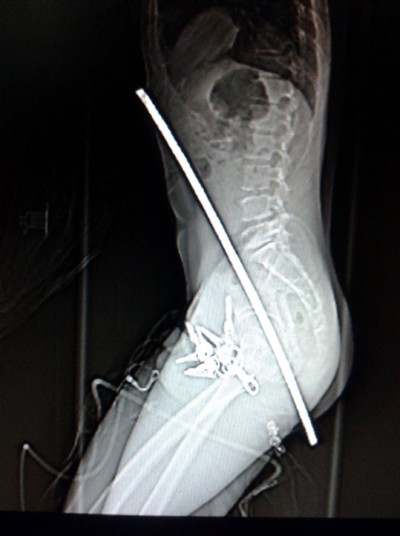

一位建筑工从3米高摔下来,从肛门插入了一个支撑杆,穿到了他的胸部。从天而降的铁棍从这名工人的后颈插入从他的左眼穿出。